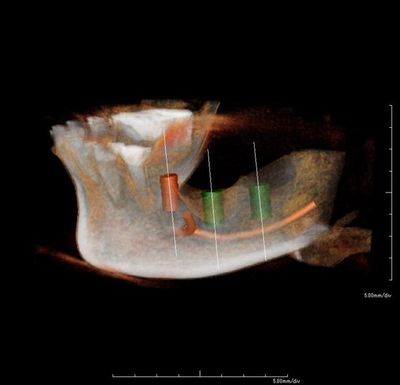

CT撮影後のシミュレーション画像です。

横に伸びているオレンジ色の線は下歯槽神経管です。

神経と血管が入っていますので絶対に損傷してはいけません。

埋入予定ポイントには骨欠損もあります。